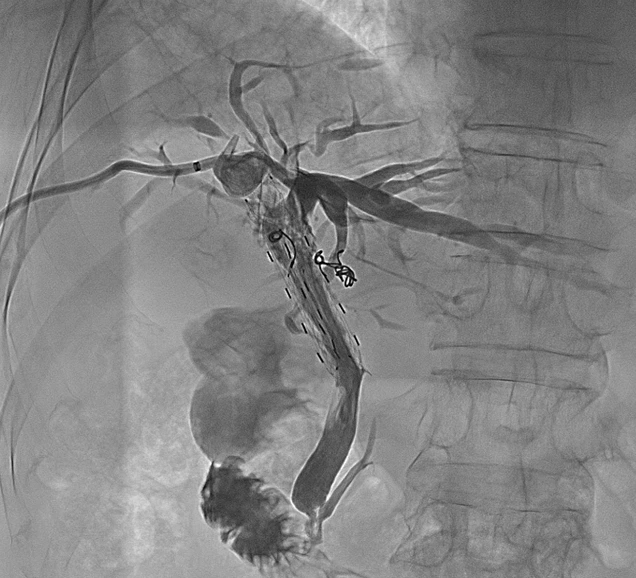

胆道粒子支架是将金属胆道支架与放射性粒子(通常为碘-125,¹²⁵I)相结合的一种创新型介入治疗手段。

持续内照射作用

支架上均匀分布的¹²⁵I放射性粒子可持续释放低能量γ射线,可在局部形成持续数月的放射治疗效应,抑制肿瘤细胞增殖、诱导肿瘤细胞凋亡。

协同效应

支架提供即时的胆道再通,放射性粒子则通过持续照射延缓肿瘤向支架腔内生长,两者协同实现更持久的治疗效果。。

将“减黄”(引流)和“抗肿瘤”(粒子)两种治疗合二为一。通常采用三腔结构,包括一个较大的胆汁引流腔和一到两个较小的粒子腔。

将携带粒子的引流管引入狭窄支架内

粒子能量在支架内局部释放,引流的同时,使支架再通